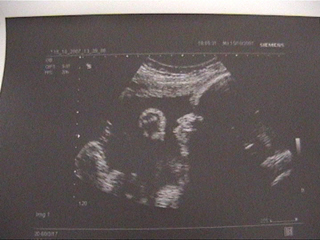

Itt van két képecske manóról, az egyiken profilból az arca eleje, az öklöcskéje és egy kicsi a lábából látszik, a másikon meg állítólag ismét a "lánysága". Én valóban, látok ott egy erősebb csíkot, valószínű, az az :D :

Edith: Szívből örülök a jó eredményeknek! :D Hatalmas a pocakod! :o Közhely, de tényleg olyan gyorsan repül az idő! Már te is 30 hetes vagy! Én a második képen több csíkot is látok, nem csak egyet ( :oops: :lol: ), az elsőn viszont nagyon szépen kivehető minden. :D

Edit! Nagyon szépek vagytok! :lol: És az UH képeken is minden simán kivehető!! Mi az, hogy "erősebb vonal"??? Az a 2 nagyajak…! :wink: :lol: